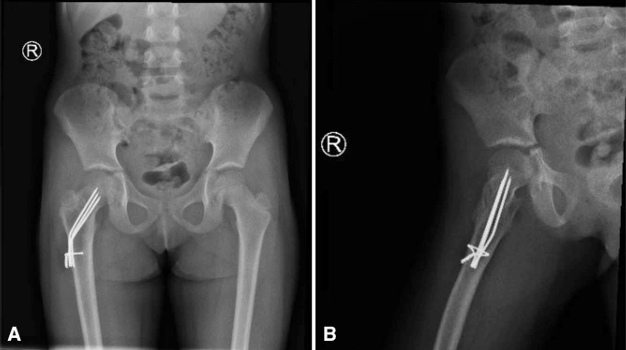

微信图片_2026-04-21_171356_618.png

Coronal MRI image demonstrating a 1.5 × 2.8 cm non-aggressive, lobulated expansile lesion in the right intertrochanteric region with a thick sclerotic rim and amorphous mineralized matrix. Periosteal reaction along the medial femoral neck suggests healing fracture changes.